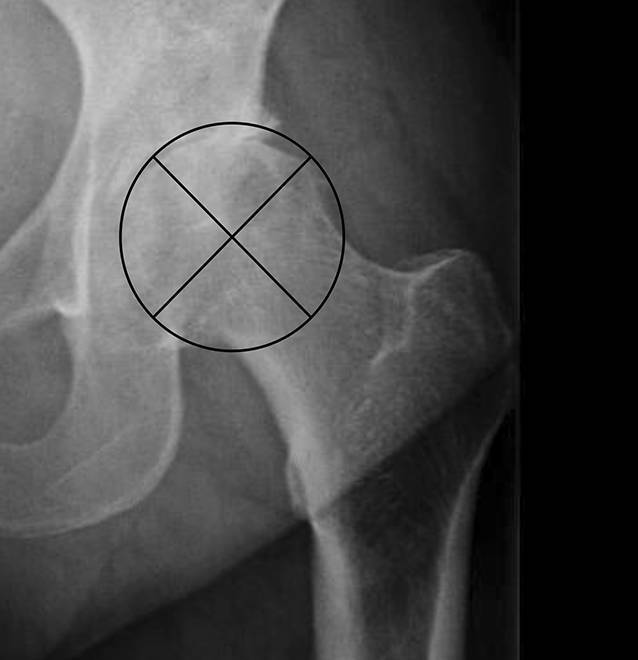

Die Qualität wurde in einem Punktesystem anhand von Kriterien bewertet, die sich aus dem präoperativen Röntgenbild bestimmen ließen. Hierbei war entscheidend, welcher Anteil des FK überhaupt zur Transplantation geeignet ist. Der FK wurde hier radiologisch in beiden Bildebenen geviertelt und zum einen der Anteil an nekrotischen/zystischen/osteolytischen Zonen, zum anderen der Anteil an deformitätsbedingtem Substanzverlust bestimmt (Abb. 2 und 3). Zusätzlich ging der intraoperative Eindruck der Knochendichte in der Sägeebene und präparierten azetabulären und femoralen Implantatlager mit in die Bewertung ein. Die klinische Beurteilung dieser Qualitäten ist wichtig, da für die meisten knöchernen Rekonstruktionen die spongiöse Knochendichte des FK einen großen Einfluss auf die Menge und insbesondere Stabilität hat.

Der FK wurde in die Größenkategorien A (>50 mm), B (>44 mm) und C (>38 mm) eingestuft, orientiert in der Untergrenze an die minimale Größe der Thermodesinfektion. Die Einstufung der Qualität erfolgte in den Stufen 1–3. Somit kann in 9 Bewertungen (A1–3, B1–3 und C1–3) unterteilt werden. Als zusätzliches Merkmal wurde das Vorhandensein eines Schenkelhalses berücksichtigt, was bei der Auswahl für ein strukturiertes Transplantat klinisch relevant sein kann.